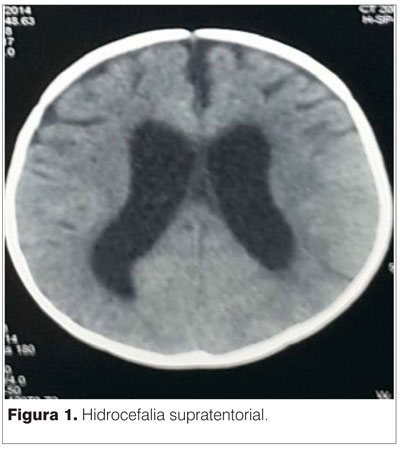

GB: 23.000 mm3/ml. Linfocitos: 59%. Hb: 11,5 g/l. Plaquetas: 868.000 mm3/ml. PCR: 6,9 mg/dl. Estudio citoquímico del líquido cefalorraquídeo (LCR): límpido, normotenso, hipoglucorraquia de 0.22 mg/dl proteínas: 1,15 g/l. PANDY +, 0 células. Tomografía computada (TC) encefálica: hidrocefalia asociada a lesiones temporales profundas (figura 1).

Síndrome de secreción inadecuado de ADH (SIADH) con hiponatremias mantenidas de hasta 123 mEq/L, tratadas con goteo de suero salino hipertónico al 3% en los primeras 72 horas. Normalización posterior. Se retira DVE a los 14 días. TC de control: hidrocefalia ventricular supratentorial, sin desplazamiento de la línea media. Resto incambiado respecto a estudios previos. Mejoría de movimientos anormales. Distermias con temperaturas axilares que oscilaban de 34-40,5 ºC durante 15 días, con cultivos negativos. Fueron interpretadas como de origen central. Requirió soporte respiratorio con AVM por 20 días, ventilación no invasiva durante cuatro, quedando luego con respiración espontánea adecuada. RxTx de control posterior normales.